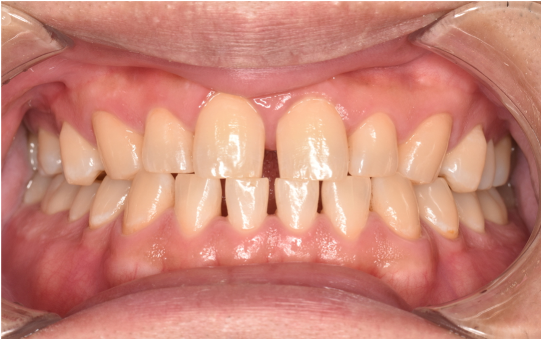

general 30代男性「タバコのヤニが気になる」縁上歯石・着色を除去し、その後歯周治療を行った症例

治療前

| カウンセリング・診断結果 | こちらの患者様は1日20本ほどタバコを吸われる方で、歯医者は十数年振りとのことでした。 縁上歯石と全体的に縁下歯石が付着しており、歯ぐきが赤く腫れ炎症しておりました。前歯の歯頸部や裏側に着色も認められました。歯周病検査により中等度の歯周炎が認められたため歯周治療も必要でした。 |